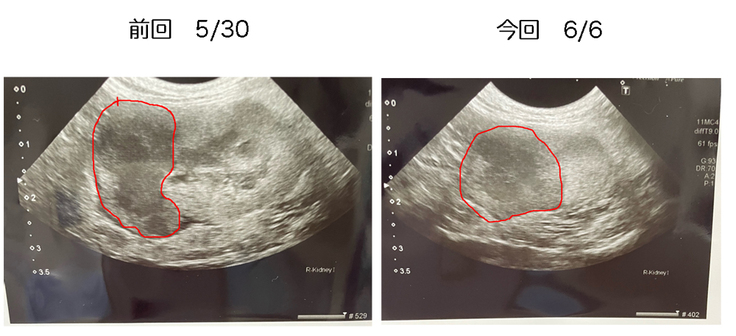

腫瘍の状態は、前回と比べ下の部分の張りが無くなっているようで、まあ良い方向に進んでいるようです。しかしながら、エコーに映る黒い部分がまだまだ大きいので、小さくなるまでには時間がかかるそうです。更に、腎臓にできる腫瘍は脳に転移する可能性が少なくないので、現在は問題ないのですが、2~3週間後の投与からは、脳への転移を抑制する事も含めた治療を始めるそうです。ここ数日は、柔らかいペースト状の食事しか摂ってくれてませんが、体重の変化もなく、比較的元気に動き回ってくれています。